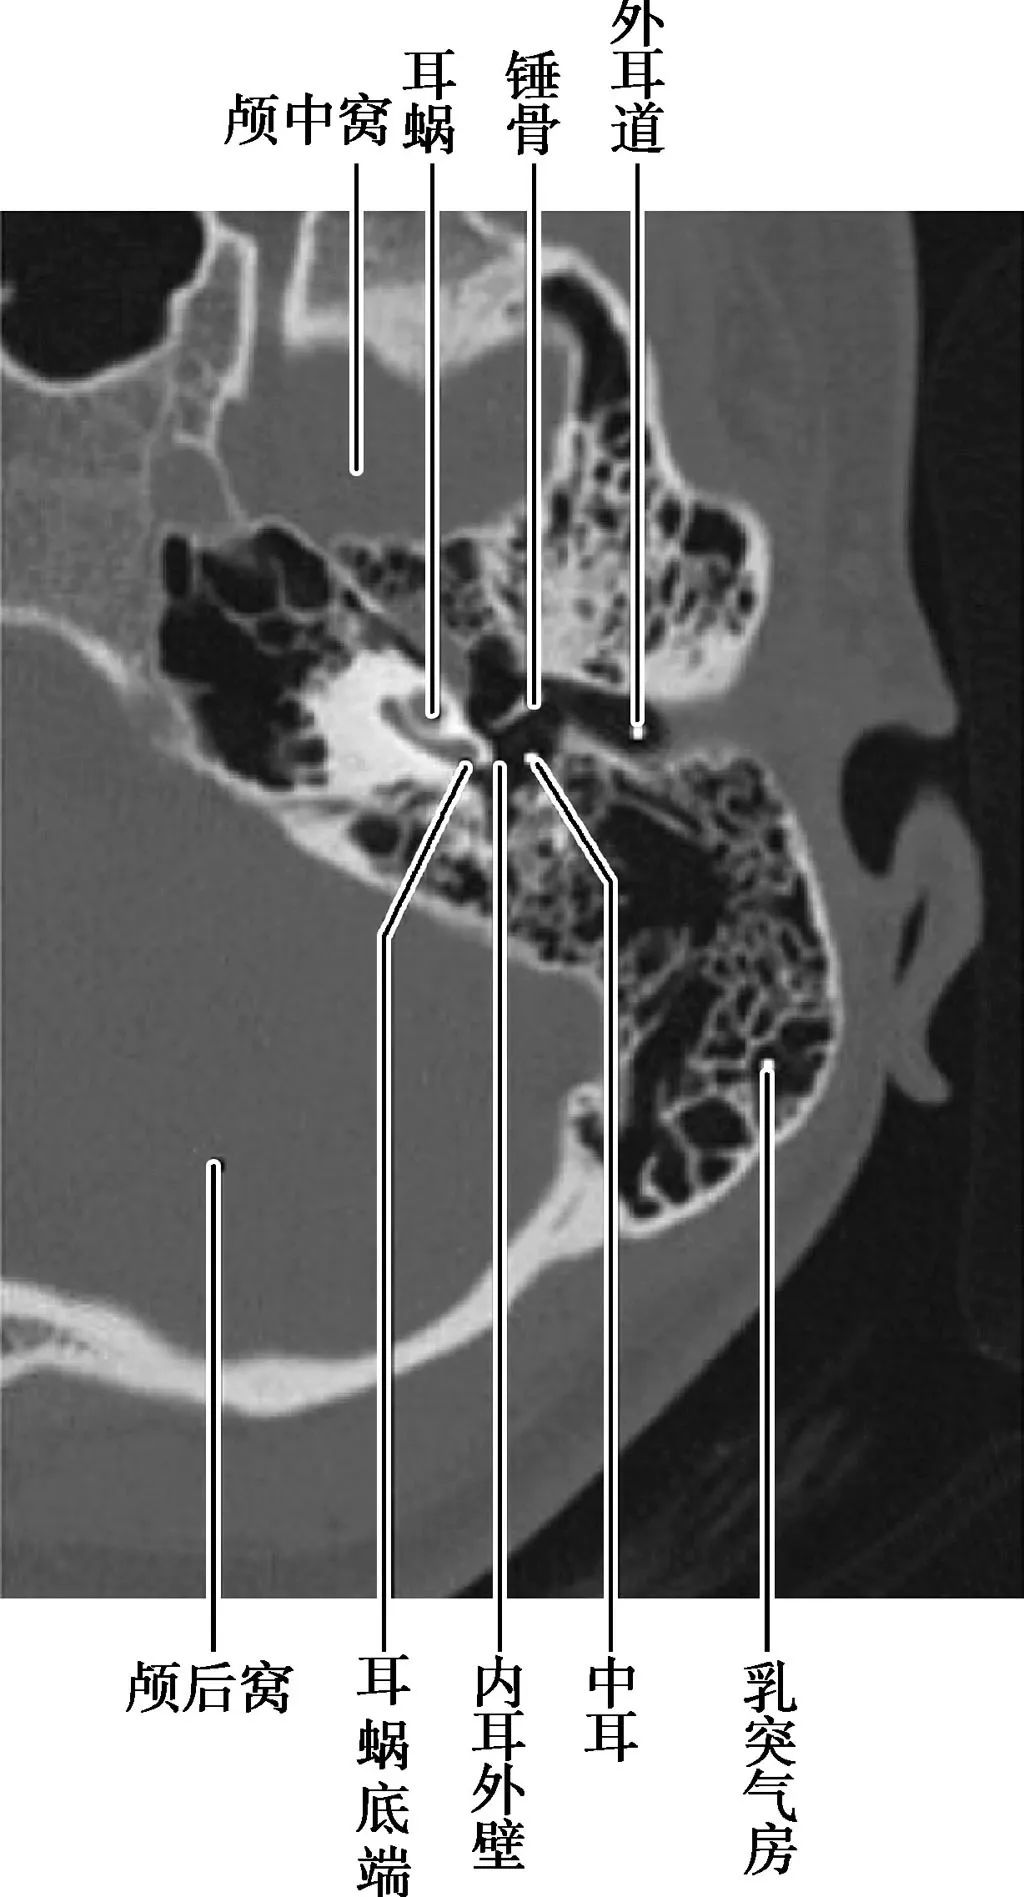

局部结构

(薄层CT)

(CT矢状面)

A.耳蜗层面;B.前庭层面;C.面神经管乳突段层面1.颈静脉球;2.内耳道;3.耳蜗;4.前庭导水管;5.后骨半规管;6.总骨脚;7.上骨半规管;8.前庭;9.面神经管迷路段;10.鼓膜张肌;11.圆窗;12.外骨半规管;13.砧骨长脚;14.锤骨颈;15.面神经管乳突段